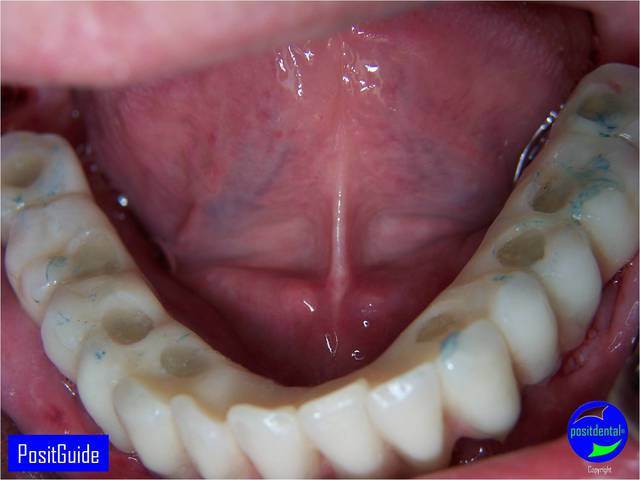

Mise en Charge Immédiate Post Extractionnelle , MCIPE partie chirurgicale de A à Z

il est en résine